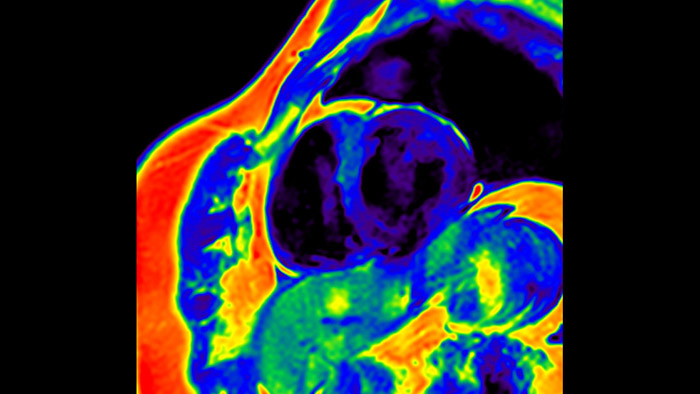

MyoStrain

Today's diagnostics often cannot detect heart dysfunction until symptoms occur. MyoStrain utilises segmental strain to measure 48 segments of the heart and provides physicians with a unique diagnostic tool to help identify regional dysfunction before the heart as a whole is affected.